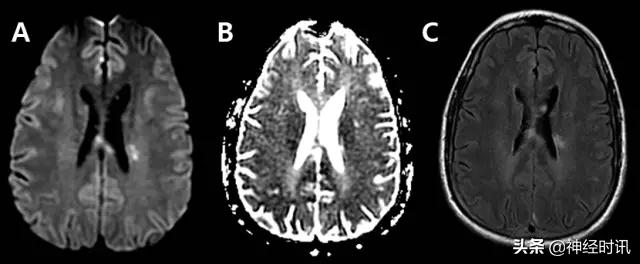

癫 痫

三分之一的卒中类似疾病是由于癫痫发作或发作后功能障碍导致。有时癫痫也可导致弥散受限(图2)。其分布特点不符合血管分布,水肿和脑回增强出现更早,脑灌注正常或增加,无血管闭塞,有时同时有皮层弥散受限和皮层下弥散增加。

图2 一例66岁男性,癫痫发作伴意识状态改变、急性失语和右侧凝视,拟诊脑卒中并给予IV-tPA治疗。左侧病灶情况下的右侧凝视可提示癫痫发作。他的入院MRI显示左侧额顶叶皮层和皮层下白质弥散受限(A和B)和水肿(C)。他的症状和影像学(图像未提供)显示在出院前完全缓解。